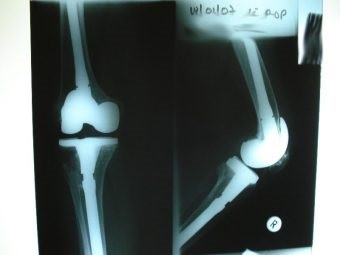

Revisión de prótesis de rodilla

Envíado por Dr. Ricardo Antonio Gómez G.